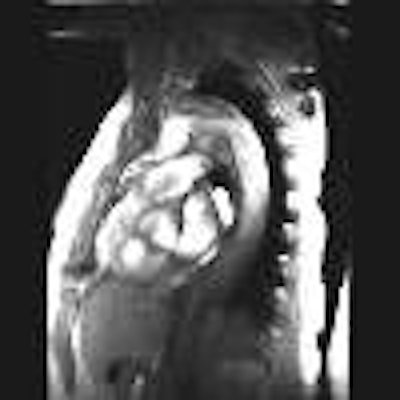

(2) Oblique sagittal SE images showing the flap originate adjacent to the origin of the left subclavian artery and

extending down into the abdomen:

(3) Oblique sagittal GRE showing flow within both the true and false lumens, and a large primary tear in the flap

in the proximal descending aorta: